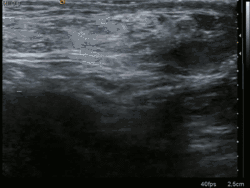

Ultrasound image of inguinal hernia. Moving intestines in the inguinal canal with respiration.

A physician may diagnose an inguinal hernia, as well as the type, from medical history and physical examination.[20] For confirmation or in uncertain cases, medical ultrasonography is the first choice of imaging, because it can both detect the hernia and evaluate its changes with for example pressure, standing and Valsalva maneuver.[21]

When assessed by ultrasound or cross sectional imaging with CT or MRI, the major differential in diagnosing indirect inguinal hernias is differentiation from spermatic cord lipomas, as both can contain only fat and extend along the inguinal canal into the scrotum.[22]